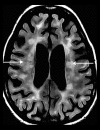

Toxic leukoencephalopathy results from damage to the white matter caused by various toxins. It manifests itself as white matter signal abnormalities with or without the presence of restricted diffusion. These changes are often reversible if the insulting agent is removed early, with the exception of posthypoxic leukoencephalopathy that can manifest itself 1-2 weeks after the initial insult. However, many other potential causes of white matter signal abnormalities can mimic the changes of toxic leukoencephalopathy. Thus, familiarity with the causes, clinical presentation and particularly imaging findings of toxic leukoencephalopathy is critical for early treatment and improved prognosis. The purpose of this pictorial essay is to familiarize the reader with the various causes of toxic leukoencephalopathy along with its differential diagnoses and mimics.